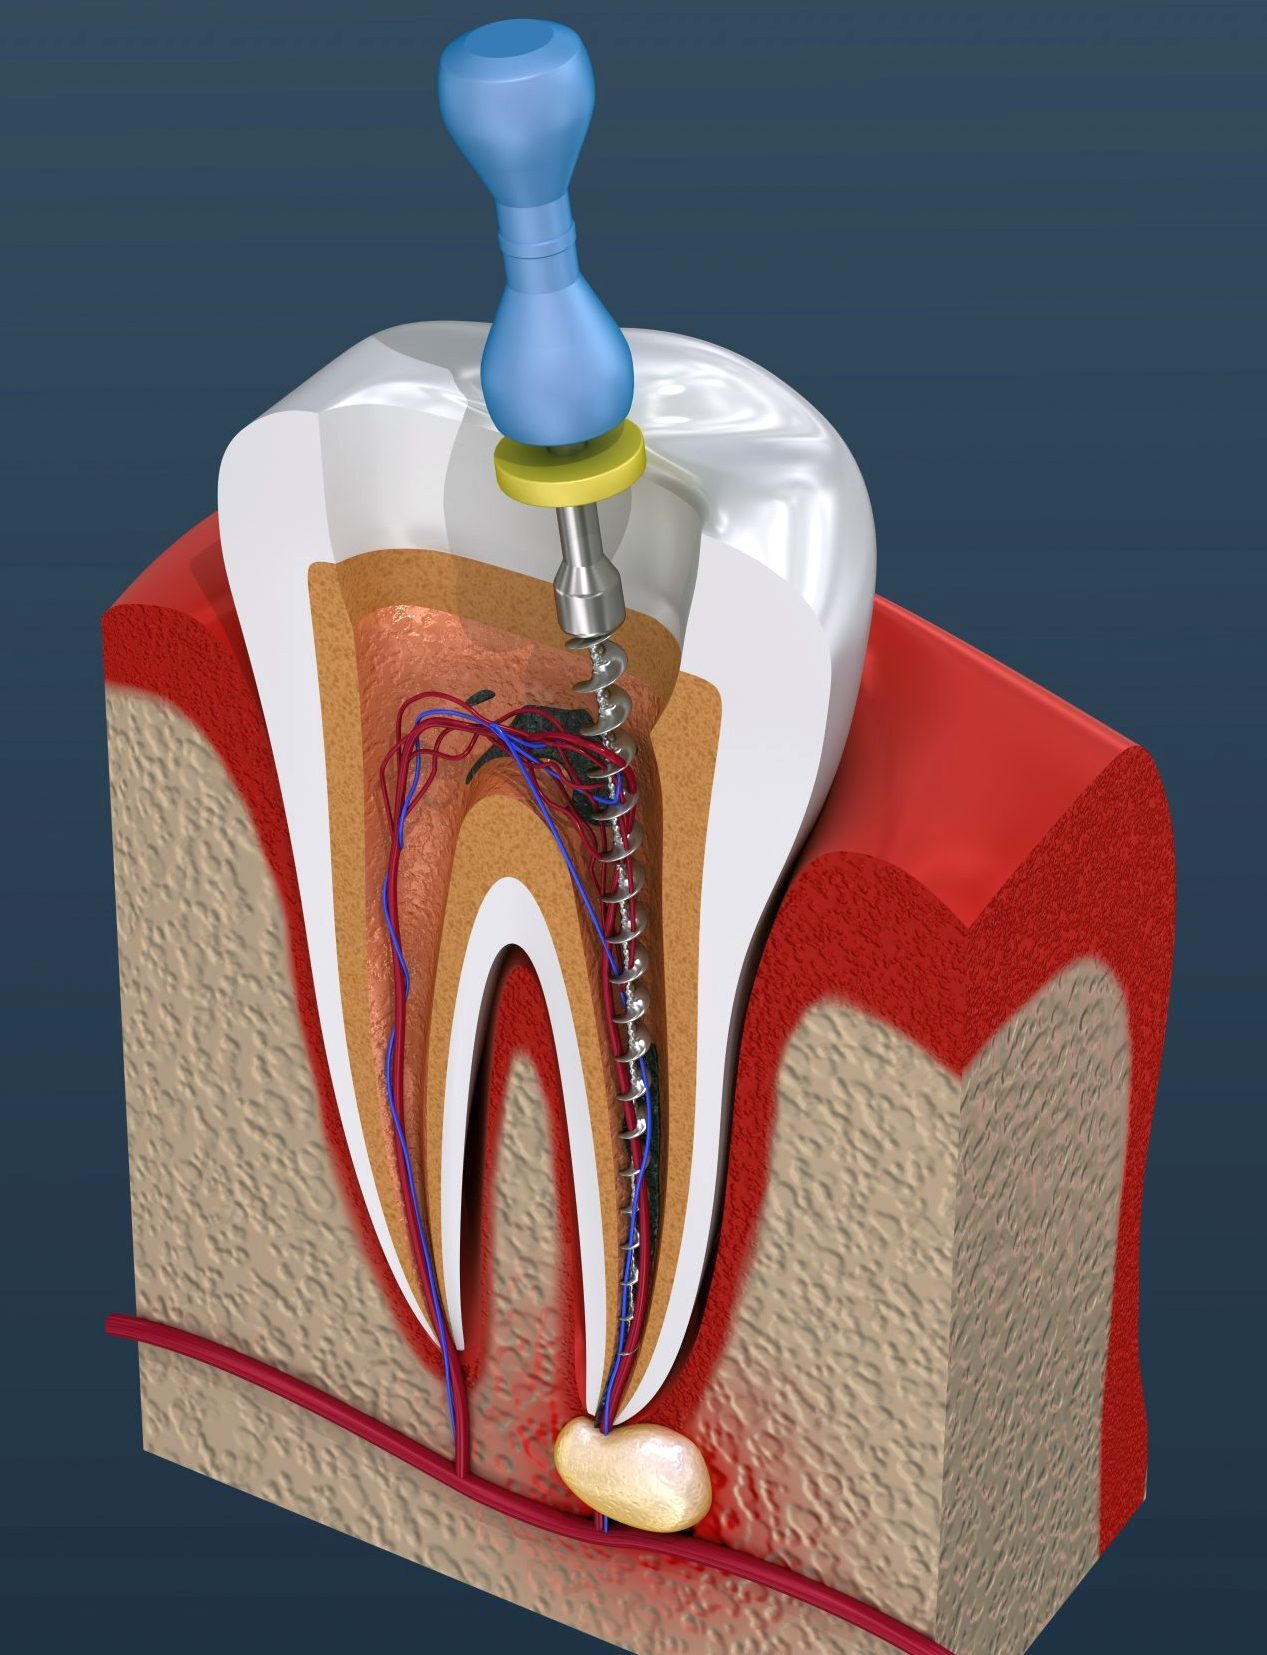

Перфорация зуба (или прободение) — это формирование патологического сообщения между внутренними полостями и каналами зуба с окружающими тканями. Образование таких отверстий может быть связано с нанесением механической травмы, либо же оно является последствием запущенного кариозного процесса.

Перфорация может локализоваться:

- в области дна зубной полости;

- в стенке зуба;

- в области зубного корня (апикальная, средняя или бифуркационная).

Перфорации в корне зуба (или зубного канала) — также одно из распространенных осложнений эндодонтического лечение, которое при неправильной лечебной тактике нередко приводит к утрате зуба.

По своей сути перфорация — это трещина (отверстие) в корне зуба, которая создает патологическое сообщение между корневым каналом и тканями периодонта.

В зависимости от места возникновения различают:

- в средней части зубного корня;

- верхушки корня зуба;

- в области бифуркации корней (между корнями зуба).